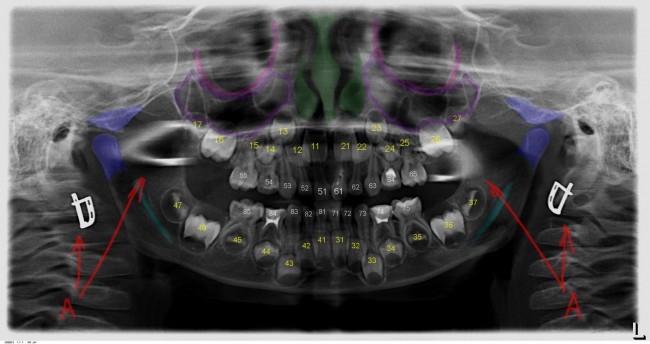

Или у детей:

У детей разряды продолжаются от правого верхнего и по часовой стрелке: «5..», «6..», «7..», «8..». Скажем, молочная пятерка слева снизу имеет номер 85.